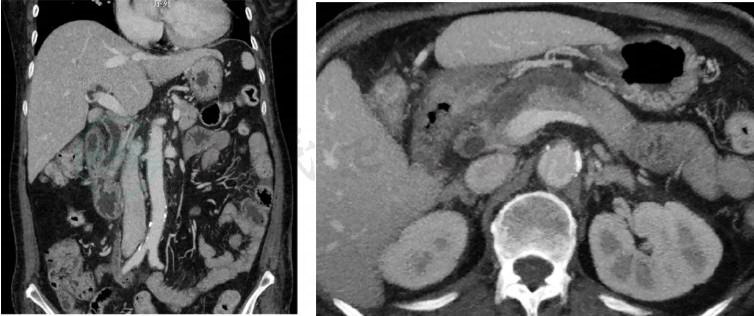

2020-03-15:当地医院腹部增强CT(图1~图3)示壶腹占位,大小约1.2cm×1.8cm,动脉期可见强化,肝内外胆管,胆总管及胰管扩张,胆总管最大内径约1.3cm,胰管最大径约0.5cm。当地医院血生化检查:白蛋白22g/L,总胆红素146μmol,直接胆红素102μmol。

图1 壶腹部占位

图2 胆总管扩张

图3 胰管扩张